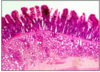

PAPILLAE AND TASTE BUDS

- dorsal tongue surface - complex folds = papillae

sweet (tip) / slaty (front/side) / sour (further back) / bitter (whole back)

filiform papillae (threadlike) - most common, tall, pointed - @ whole anterior 2/3

fungiform papillae (mushroom-like) @ tip and sides

- @ lateral side fungiform papillae = pale-staining, spindle-shaped taste buds w/ nerves/synaptic vesicles

circumvallate papillae (V-shaped row) @ divide between anterior 2/3 and post. 1/3

this slide - 2 paler staining taste buds embedded in opposing sides of adjacent fungiform papillae